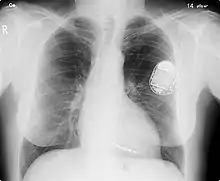

النَّاظِمَة[1] أو النَّاظِمَة القَلْبِيَّة[1] أو منظّم ضربات القلب (بالإنجليزية: pacemaker) أو الناظمة القلبية الاصطناعية[1] أو منظّم ضربات القلب الاصطناعي (بالإنجليزية: artificial pacemaker)، لكي لا يختلط المفهوم بمنظّم ضربات القلب الطبيعي) هو عبارة عن جهاز طبي يستخدم تَدَفُّعاتُ كهربائية، تصل عبر أقطاب تضمن انقباض عضلات القلب، لتنظّم ضربات القلب.

إن الغرض الأساسي من منظّم ضربات القلب هو المحافظة على معدل ضربات القلب بشكل كافي، إما لأن سرعة منظّم ضربات القلب الطبيعي غير كافية، أو أن نظام التوصيل الكهربائي للقلب به إحصار. منظم ضربات القلب الحديث قابل للبرمجة خارجيا بحيث يسمح لطبيب القلب تحديد صيغة الإنظام لكل مريض على حدة. بعض الأجهزة تحتوي على منظّم ضربات القلب ومُزيلُ الرَّجَفان في جهاز واحد. والبعض الآخر يحتوي على أقطاب متعددة تقوم بتنبيه مواقع متباينة داخل القلب وتحسّن بدورها تزامن البطينين في القلب.

إنظام دائم بناظمة مزروعة تتطلب إدخال عبر الوريد لقطب أو أكثر في حجرة من حجرات القلب أو أكثر، والجهاز مزروع تحت الجلد أسفل عظمة التَرْقُوَة. يتم تنفيذ العملية عن طريق شق الوريد المناسب ومن ثم إدخال سلك القطب ليمر على طول الوريد، من خلال صمام القلب، حتى وضعه في إحدى حجرات القلب. إن هذه العملية مدعمة بتوجيه التَنْظيرٌ التَأَلُّقِيّ (Fluoroscopy) والذي يتيح للطبيب رؤية مرور سلك القطب. بعد التأكد من إيداع القطب بصورة مرضية يتم إيصال الطرف الآخر منه في مولد الناظمة هناك ثلاثة أنواع أساسية من الناظمات الدائمة، مصنفة وفقا لعدد الحجرات المكتنفة وآلية عملها:[32]